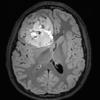

NEOPLASMS (EMBRYONAL)

CNS-BCOR ITD (2)